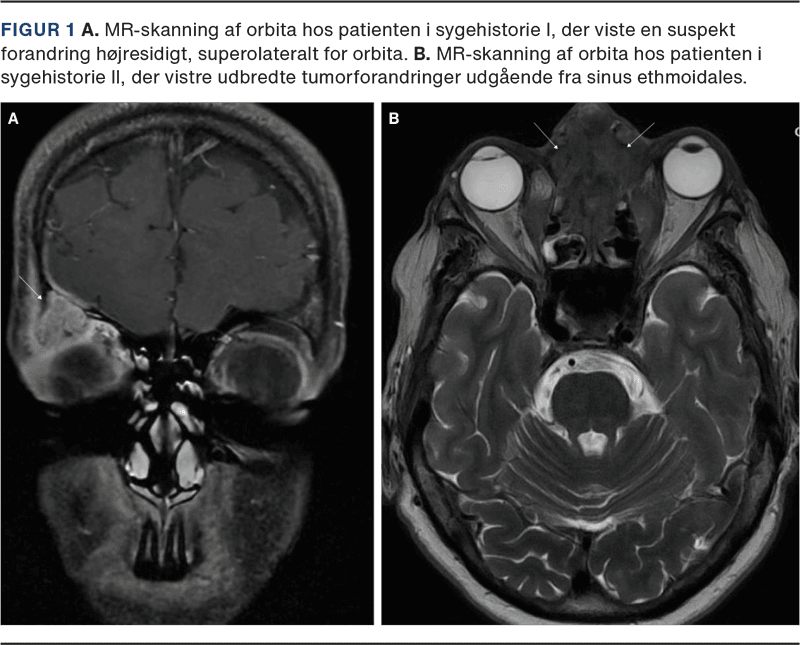

I. En otteårig, ellers sund og rask pige blev henvist til øjenafdelingen på grund af rødme og hævelse omkring det højre øje igennem en måned. Der var ingen næse-bihule-symptomer eller symptomer i øvrigt, og behandling med fusidin-creme eller phenoxymethylpenicillin havde ingen effekt. Objektivt fandtes rødme og hævelse omkring det højre øje, visus 1,0, normal tension, farvesyn, H-konfiguration, naturlig spaltelampeundersøgelse og oftalmoskopi. Patienten blev opstartet i amoxicillin/clavulansyre efter vægt på mistanke om præC. Grundet manglende fremgang efter endt kur blev der udredt med MR-skanning af orbita. Denne viste en 15 × 16 × 12 tumorsuspekt forandring superolateralt i orbita (Figur 1 A). Patienten blev henvist til Øjensygdomme, Aarhus Universitetshospital, og herfra videre til Neurokirurgisk Afdeling. På udredningstidspunktet på Neurokirurgisk Afdeling, hvor der var gået ca. tre uger, var hævelsen svundet helt. Ved gennemgangen af skanningen var der mistanke om, at forandringen kunne repræsentere et mucocele. Kontrol-MR-skanning tre måneder efter viste fuld regression af forandringen.

II. En 57-årig kvinde blev henvist til øjenafdelingen, obs venstresidig dacryocystitis. Patienten havde gennem en måned en voksende hævelse ved den øvre, mediale øjenkrog uden smerter eller feber. Hun blev opstartet i amoxicillin/clavulansyre, og grundet manglende fremgang på behandlingen og den atypiske placering ved den øvre del af næseryggen blev der henvist til MR-skanning af orbita. Skanningen viste udbredte tumorforandringer i sinus ethmoidales (Figur 1B), kranielle del af cavum nasi og medialt i begge orbita. Canceren havde udgangspunkt i etmoidalcellerne og var på stadie T4b, N1, M0. Patienten blev opstartet palliativt i højdosisstråleterapi og kemobehandling.